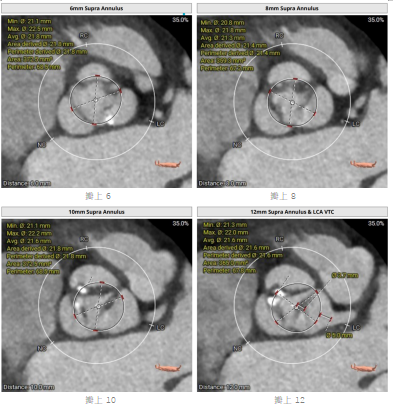

为确保手术安全有效,术前,团队为患者进行了精细的心脏CTA扫描,并运用先进的三维重建技术,对患者的主动脉根部解剖结构、瓣膜钙化程度、冠状动脉开口位置及入路血管条件进行了全方位、立体化的“术前推演”。

评估结果极其复杂:患者为功能性二叶瓣,R-N交界高位融合,瓣叶增厚伴重度钙化,钙化主要分布于右无窦交界区,左室流出道呈直筒型,瓣膜锚定难度较大,术中面临瓣膜移位、瓣周漏、冠状动脉阻塞等多重风险。心血管内科团队联合心外科、影像科、超声科、麻醉科、体外循环科、介入导管室等多学科专家,基于患者病情及CTA精确测量结果,术前联合分析并制定了详细的手术策略,包括手术流程及释放技巧、左冠保护方案以及循环崩溃的应急预案。